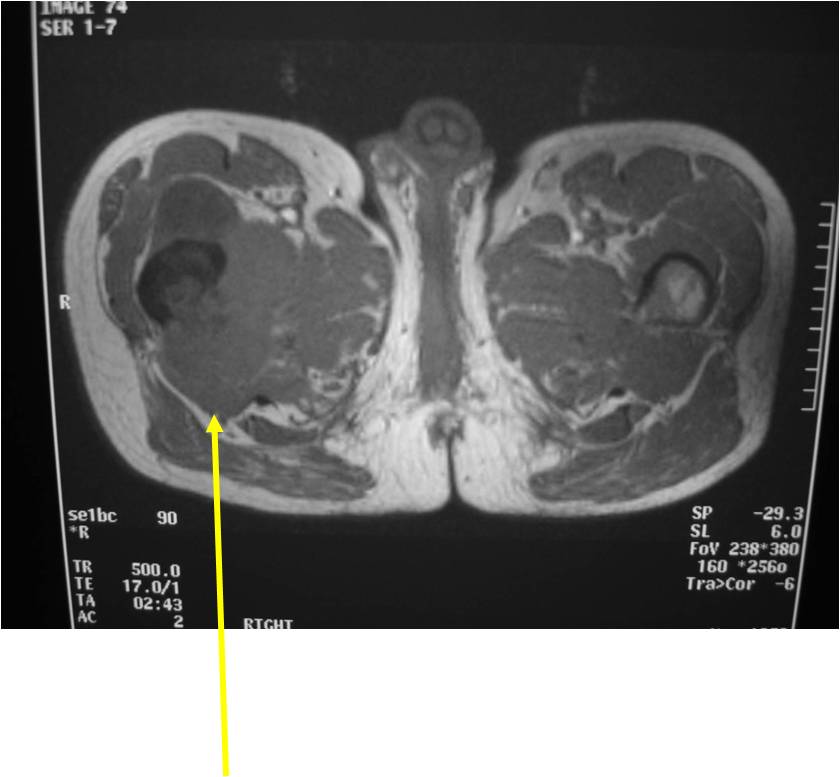

Radiographic Presentation

Radiology emulates pathology: Biphasic Tumor

- One region low grade chondrosarcoma

- Second more aggressive area with bone destruction, lysis of calcification, soft tissue mass

- Cortical permeation and a soft tissue mass in 70% of cases

Ill-defined, lytic intraosseous lesion

- Or extraosseous soft tissue mass

- Devoid of calcifications in continuity with lesions having the features of a cartilaginous tumor

Characteristically abrupt transition between chondroid tumor and dedifferentiated, lytic component

Bone may be expanded and adjacent cortex thickened

(Right Arrow)Aggressive Lytic Area (Dedifferentiated Sarcomatous Component) Cortical Destruction Soft Tissue Mass without Calcification